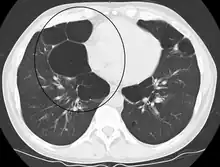

Advanced centrilobular emphysema showing total lobule involvement on the left side

Centrilobular emphysema, also called centriacinar emphysema, affects the centre of a pulmonary lobule (centrilobular) in the lung, the area around the terminal bronchiole and the first respiratory bronchiole, and can be seen on imaging as an area around the tip of the visible pulmonary artery. Centrilobular emphysema is the most common type usually associated with smoking, and with chronic bronchitis.[17] The disease progresses from the centrilobular portion, leaving the lung parenchyma in the surrounding (perilobular) region preserved.[24] Usually the upper lobes of the lungs are affected.[17]